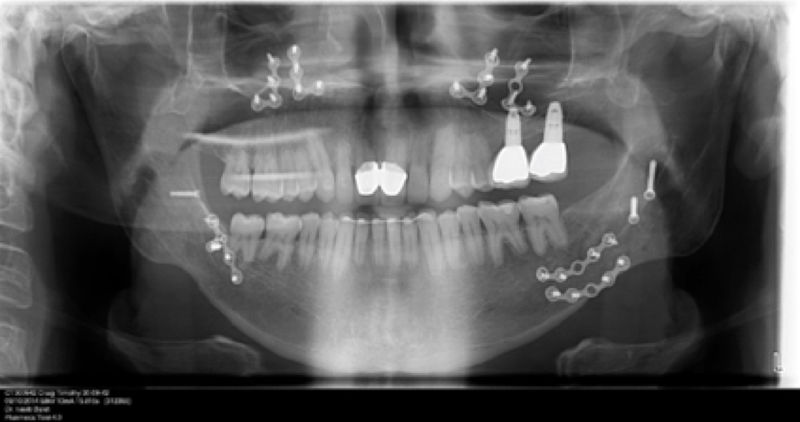

En Prótesis Integral trabajamos con equipos de última tecnología: radiología digital, impresiones digitales, implantología moderna y laboratorios con CAD/CAM. Todo ello nos permite ofrecer soluciones duraderas, precisas y estéticas en un entorno de confianza, seguridad y calidez humana.

Los implantes dentales son pequeños tornillos de titanio u otro material biocompatible que se insertan en el hueso maxilar o mandibular para sustituir la raíz de un diente perdido. Actuando como un soporte sólido sobre el cual el dentista puede colocar un diente artificial (corona), un puente o una prótesis completa.

Son estructuras de titanio las cuales se colocan en el hueso y se utilizan para soportar coronas, prótesis fijas, removibles y totales. La colocación de los implantes se hacen previo análisis tomográfico.

Implantes, ortodoncia y coronas.

Cirugía ortognática, implantes, carillas y coronas,